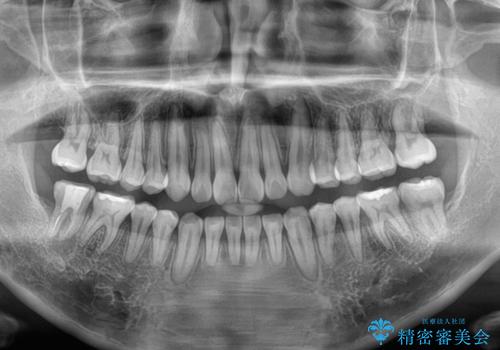

一年と数か月で矯正を終えることができました。

下顎前歯部には後戻り防止のワイヤーを装着しています。